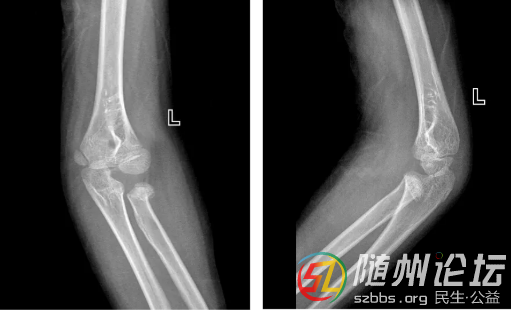

[本地醫(yī)療] 女童肘部“雙重骨折”,微創(chuàng)手術(shù)護(hù)佑健康成長(zhǎng)

近日,隨州市中心醫(yī)院創(chuàng)傷骨科與小兒骨科接診了一位9歲的小患者安安(化名)。她在玩耍時(shí)不慎摔倒,導(dǎo)致肘部腫脹、劇痛。經(jīng)檢查發(fā)現(xiàn),安安的傷情較為復(fù)雜,為橈骨小頭骨折合并尺骨鷹嘴骨折,屬于肘部“雙重骨折”。這一結(jié)果讓家長(zhǎng)十分擔(dān)憂。

考慮到兒童骨骼尚在發(fā)育,治療需格外注重對(duì)生長(zhǎng)能力的保護(hù),安安的父母選擇來(lái)到隨州市中心醫(yī)院創(chuàng)傷骨科與小兒骨科尋求進(jìn)一步診治。接診的副主任醫(yī)師陳康詳細(xì)解釋道:“孩子摔倒時(shí)手臂伸直撐地,沖擊力會(huì)同時(shí)傷及肘關(guān)節(jié)兩個(gè)關(guān)鍵結(jié)構(gòu):一是負(fù)責(zé)前臂旋轉(zhuǎn)的‘軸心’—橈骨小頭;二是主管肘關(guān)節(jié)屈伸的‘掛鉤’—尺骨鷹嘴;這兩處同時(shí)骨折,會(huì)嚴(yán)重影響肘部功能。根據(jù)影像檢查,保守治療難以維持穩(wěn)定復(fù)位,但通過(guò)微創(chuàng)手術(shù)結(jié)合早期康復(fù)治療,孩子通常能恢復(fù)得很好?!?br />

針對(duì)安安的骨折類型,陳康醫(yī)師為她量身制定了微創(chuàng)手術(shù)方案:采用橈骨彈性髓內(nèi)釘聯(lián)合尺骨鷹嘴螺釘內(nèi)固定術(shù)。手術(shù)僅通過(guò)幾個(gè)微小切口完成,極大降低了創(chuàng)傷,更重要的是有效保護(hù)了骨骺(生長(zhǎng)板),避免了對(duì)其未來(lái)骨骼生長(zhǎng)發(fā)育的影響。